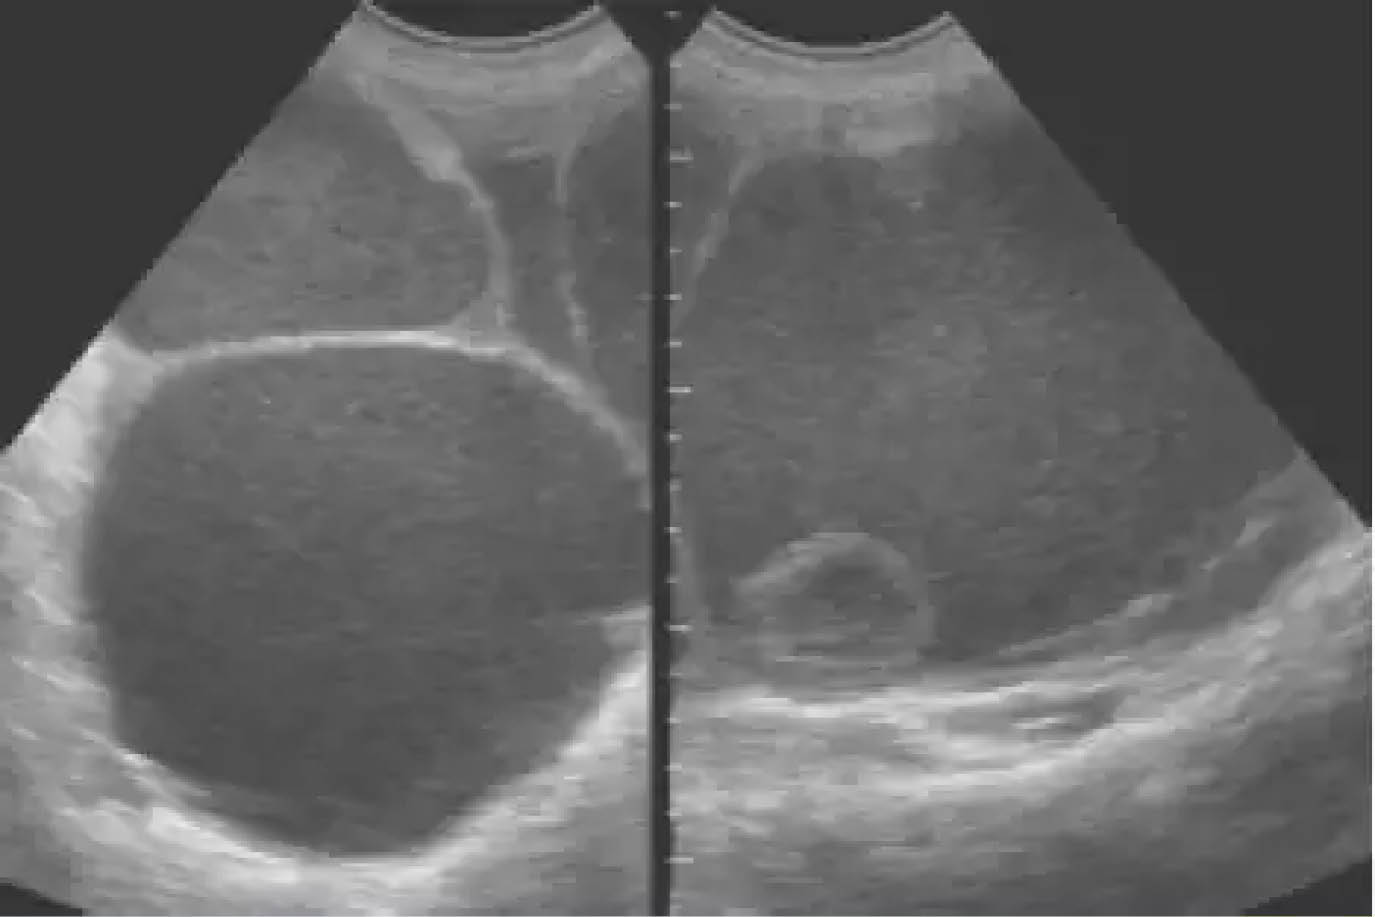

El presente caso es sobre una niña de 13 años sin antecedentes patológicos se palpo una masa tensa e indolora que ocupaba hipogastrio al epigastrio, una ecografía doppler y una TAC mostró un tumor quístico pélvico-abdominal de 25×25 cm con escasa vascularización.

Se prefirió abordaje por Pfannestiel sin sección muscular obteniéndose 1800 cm3 de liquido filante y se exteriorizo el tumor que reemplazaba el ovario izquierdo, el epiplón mayor, el ovario derecho eran normales, no había denomegalias, se realizó salpingo-oforectomia izquierda informándose cistoadenoma mucinoso borderline.